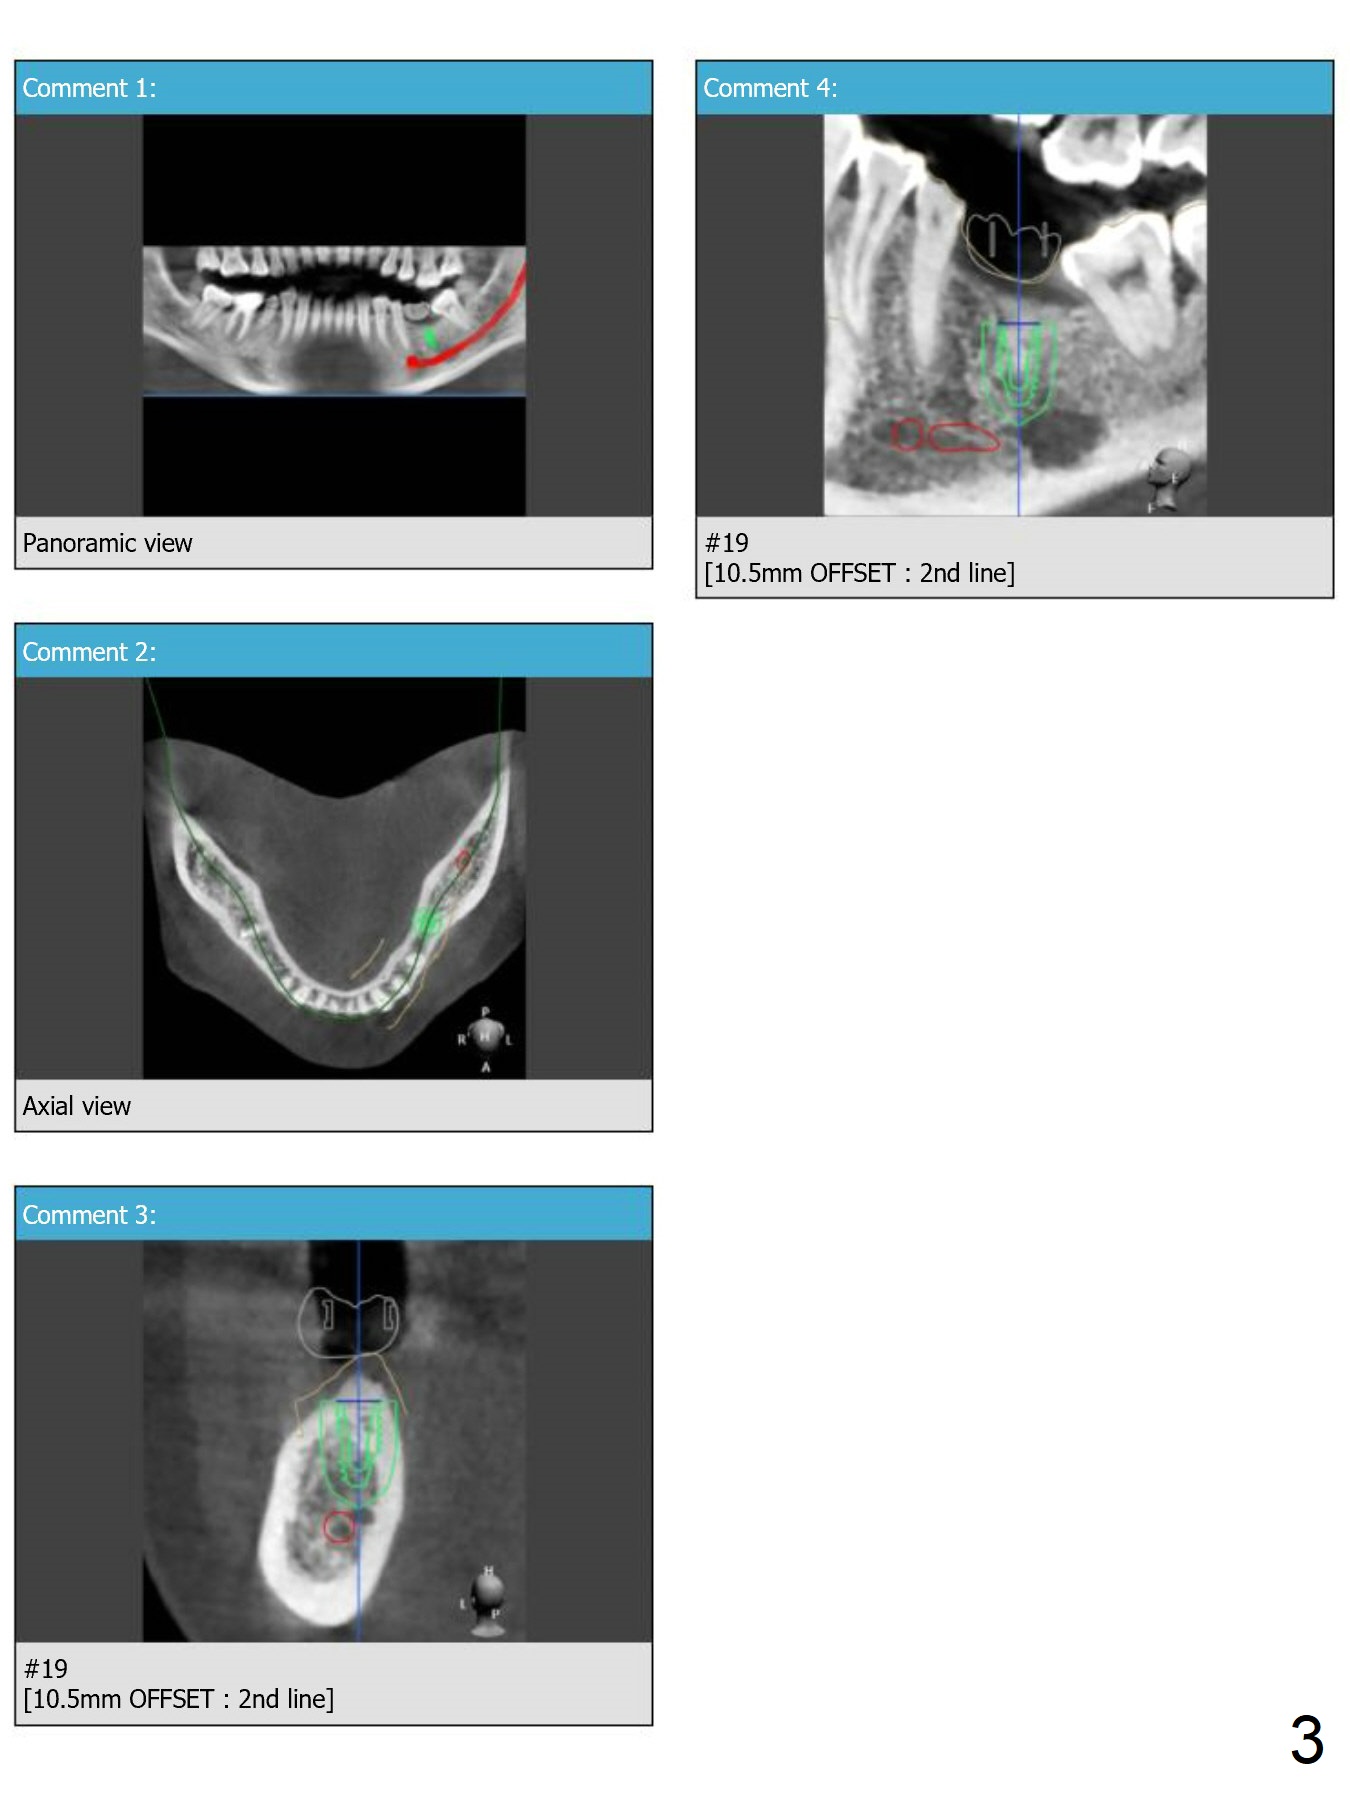

Guided surgery will be conducted at #19 post mini-implant placement for the opposing tooth intrusion.